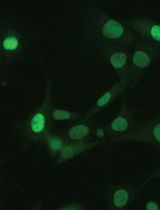

This protocol has merit to observe the subretinal microglia or macrophages (Figure 5), which are separated to retina and/or choroid/RPE whole mounts in the general protocol. See additional resources for a demonstration of subretinal microglia and extended processes (Kim et al., 2016).

Figure 5. Subretinal microglia in Sclerochoroid/RPE/Retina whole mount. Sclerochoroid/RPE/Retina tissues are labeled by phallodin-488 (green), CD11b antibody (red) and Hoechst 33342 (blue). Images were captured from choroid/RPE to the upper level of photoreceptor layer, every 2 μm z-interval. A. A projected image. B. Images arranged at 4 μm interval. Arrow heads indicate migrating/extending processes of microglia from the photoreceptor layer to the subretina. Ph, photoreceptors; RPE, retinal pigment epithelium. Scale bar, 50 μm.